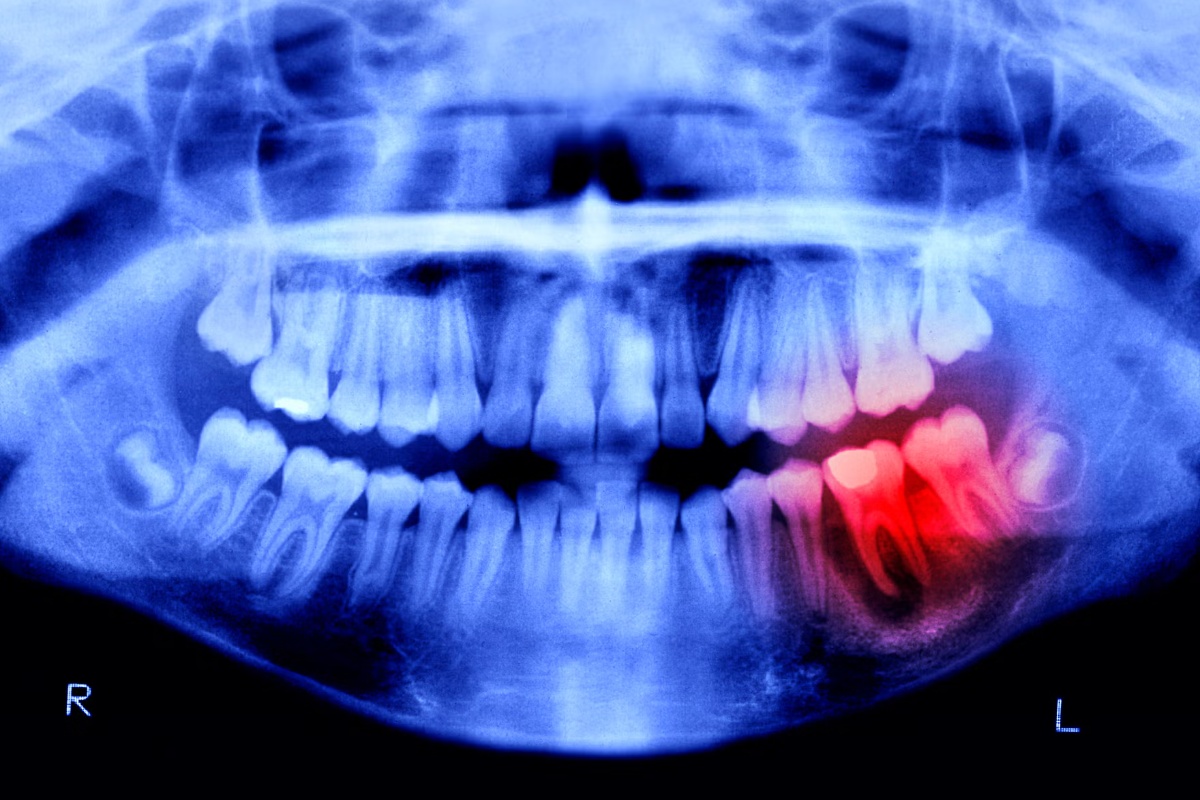

Japanski istraživači napreduju s eksperimentalnim lijekom koji obećava rast novih ljudskih zubi. Klinička ispitivanja na ljudima započela su u rujnu 2024. godine, donoseći nadu milijunima ljudi diljem svijeta koji pate od edentalizma, odnosno bezubosti.

Ovaj nevjerojatan napredak uslijedio je nakon godina proučavanja specifičnog antitijela nazvanog USAG-1 (Uterine sensitization–associated gene-1). Znanstvenici su otkrili da ovo antitijelo blokira rast zubi kod miševa i feretki. Još 2021. godine, znanstvenici sa Sveučilišta u Kyotu otkrili su monoklonsko antitijelo koje prekida interakciju između USAG-1 i molekula poznatih kao koštani morfogenetski protein (BMP).